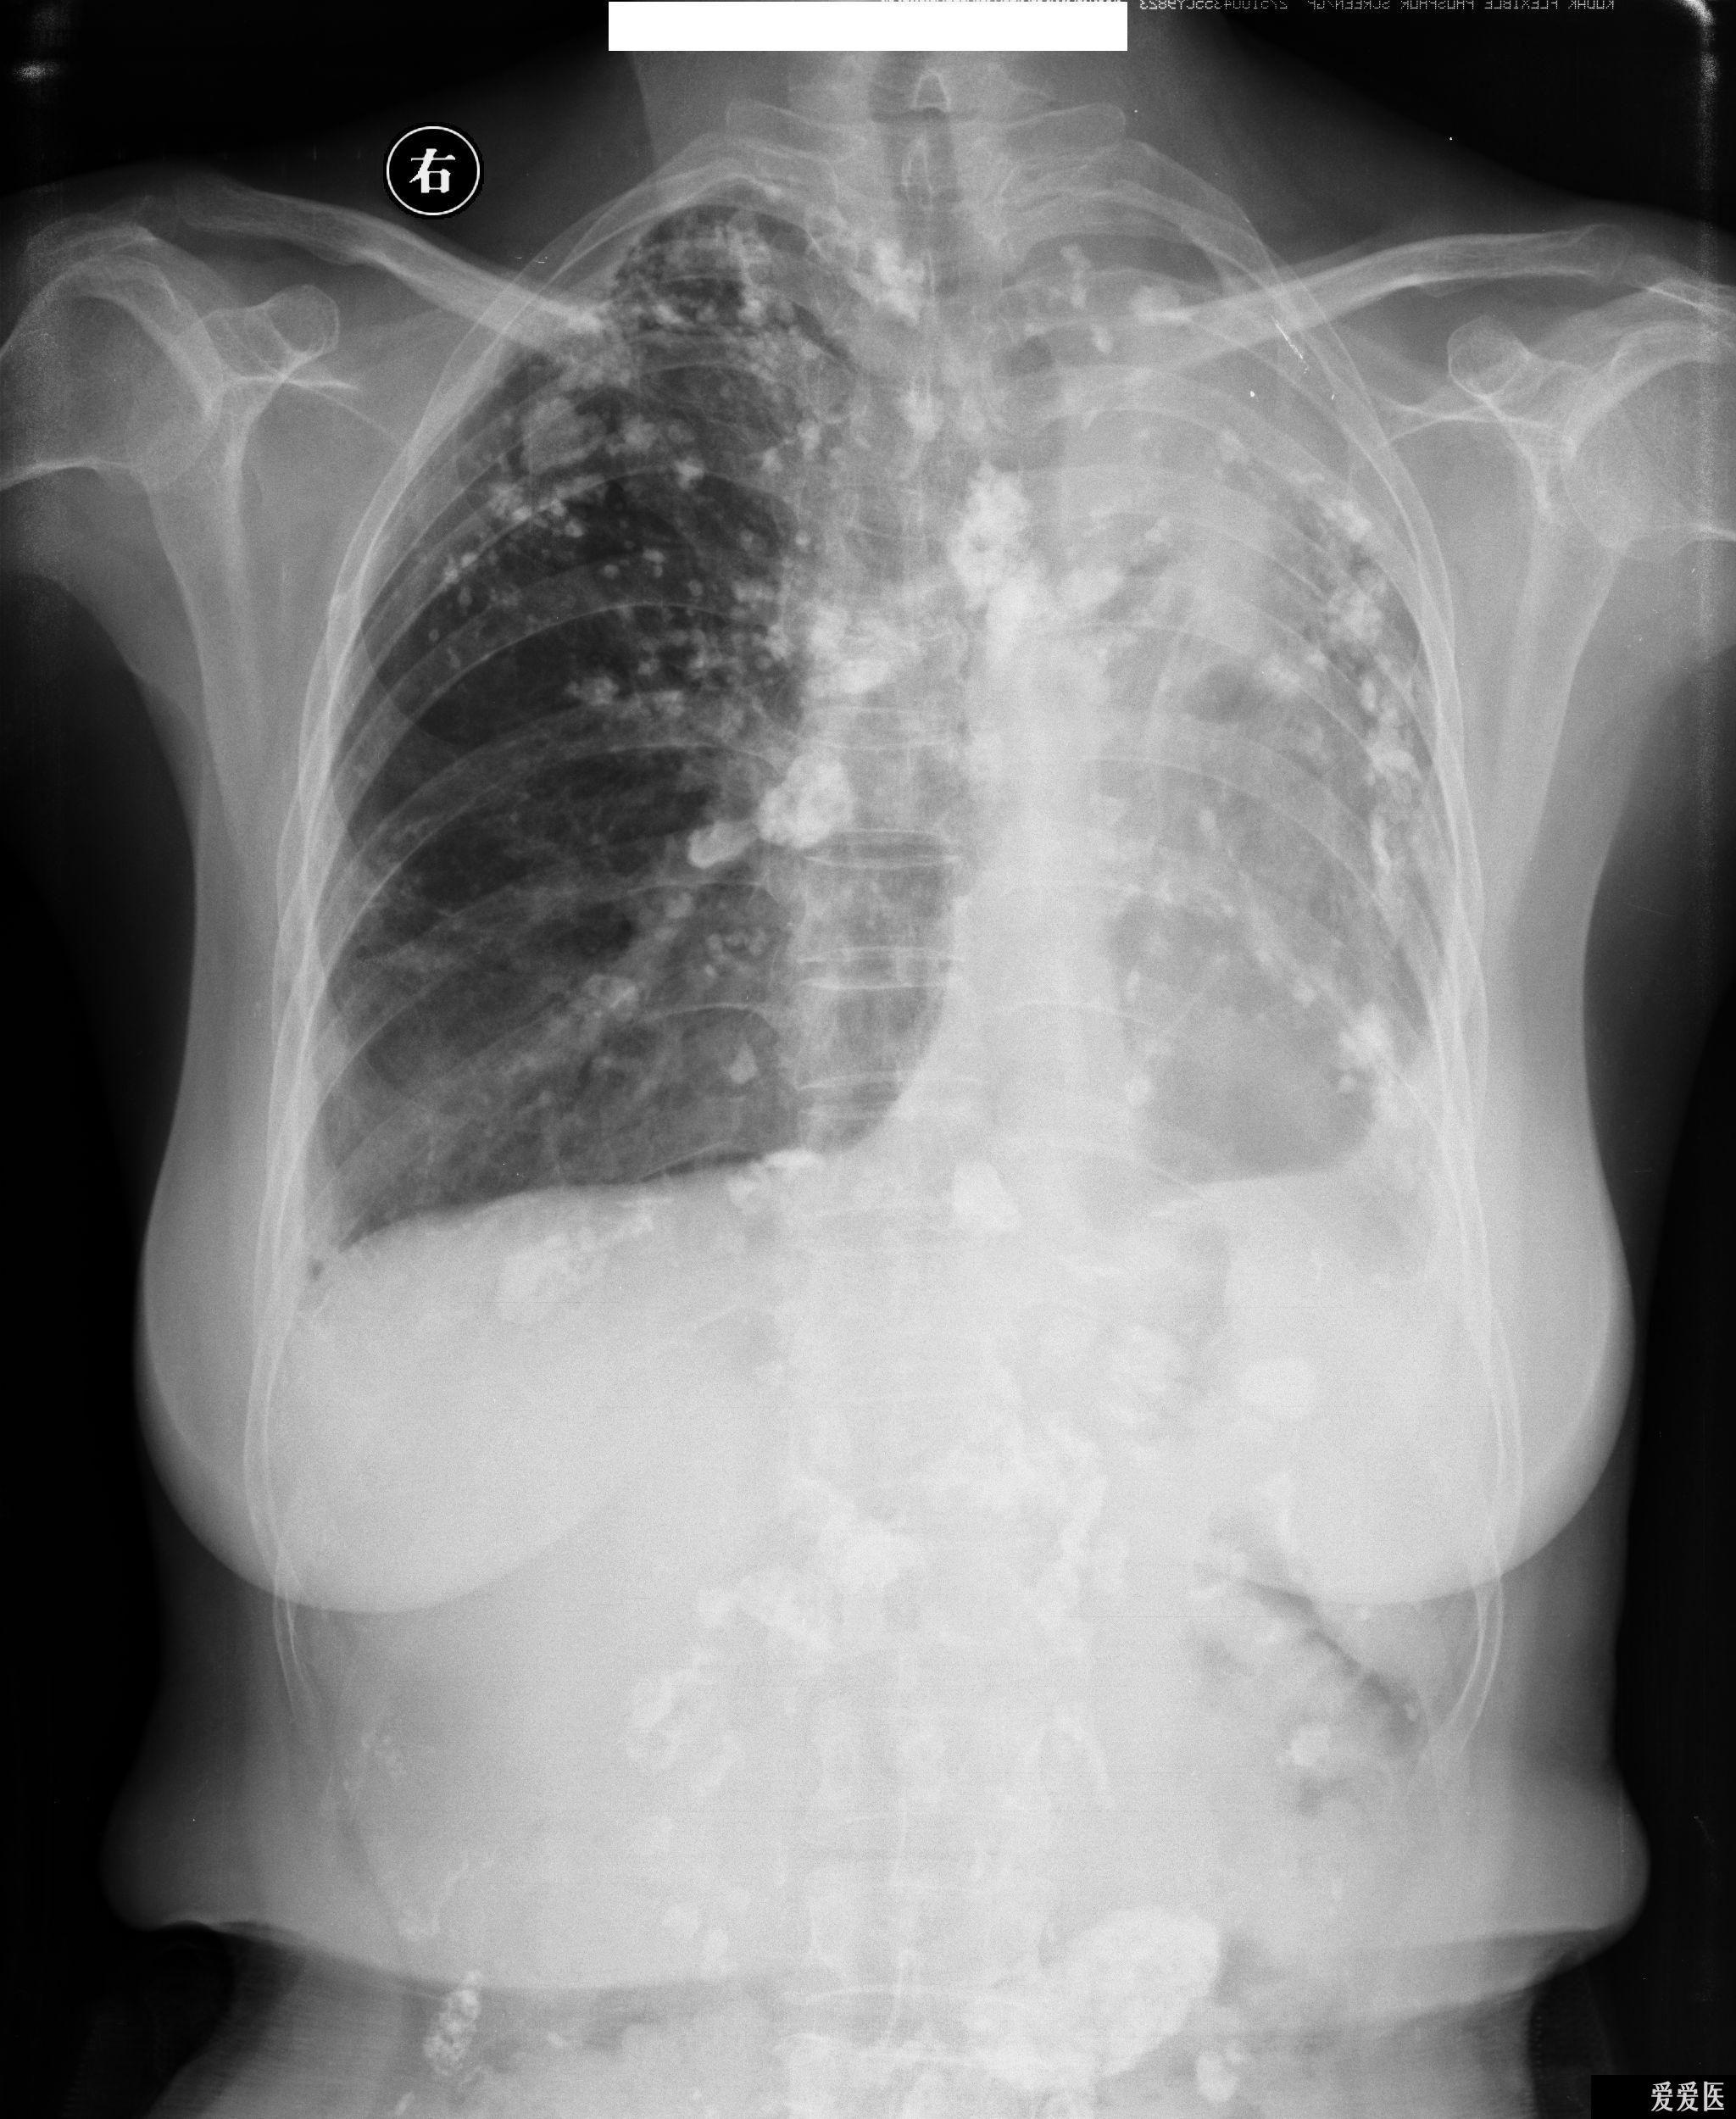

之后拍摄胸片:

双侧胸腔散在广泛钙化,左肺萎缩,心脏纵膈向左侧移位。

X线诊断:结合腹部X线征象,为双肺陈旧性肺结核并胸腔、腹腔淋巴结钙化;左肺萎缩;左侧胸膜增厚、钙化致左胸廓塌陷。